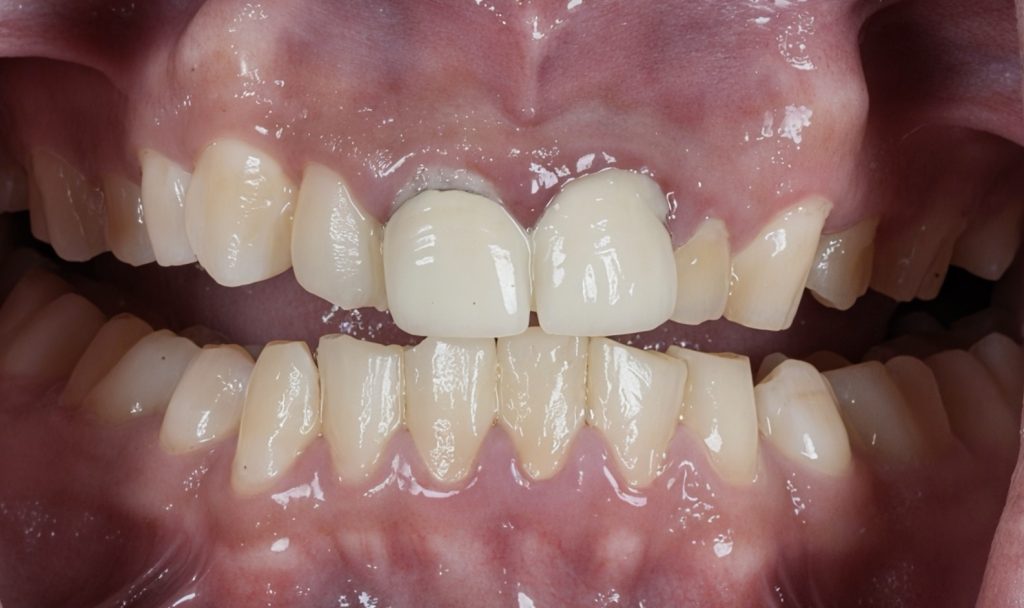

Final Outcome

- Natural shape and symmetry restored

- Improved occlusion and anterior guidance

- Stable gingival profile

- Lifelong color stability and strength from Emax

- Patient reported instant aesthetic and functional improvement